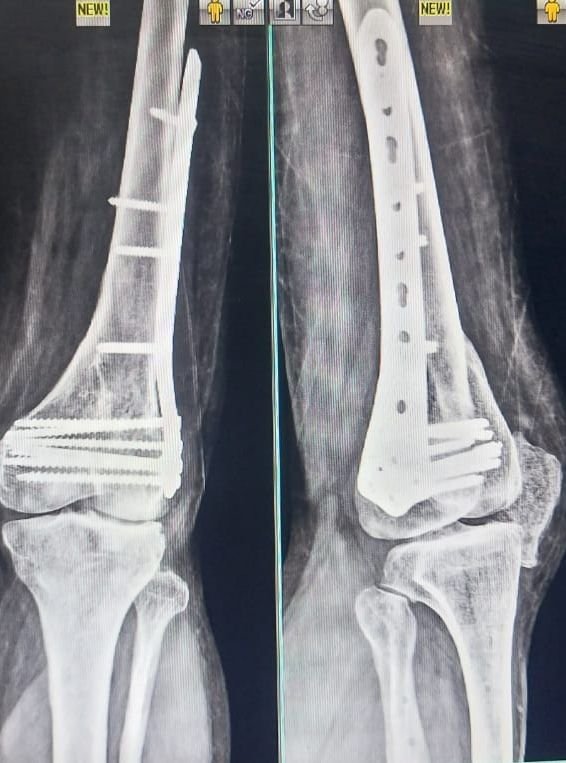

Knee Replacement